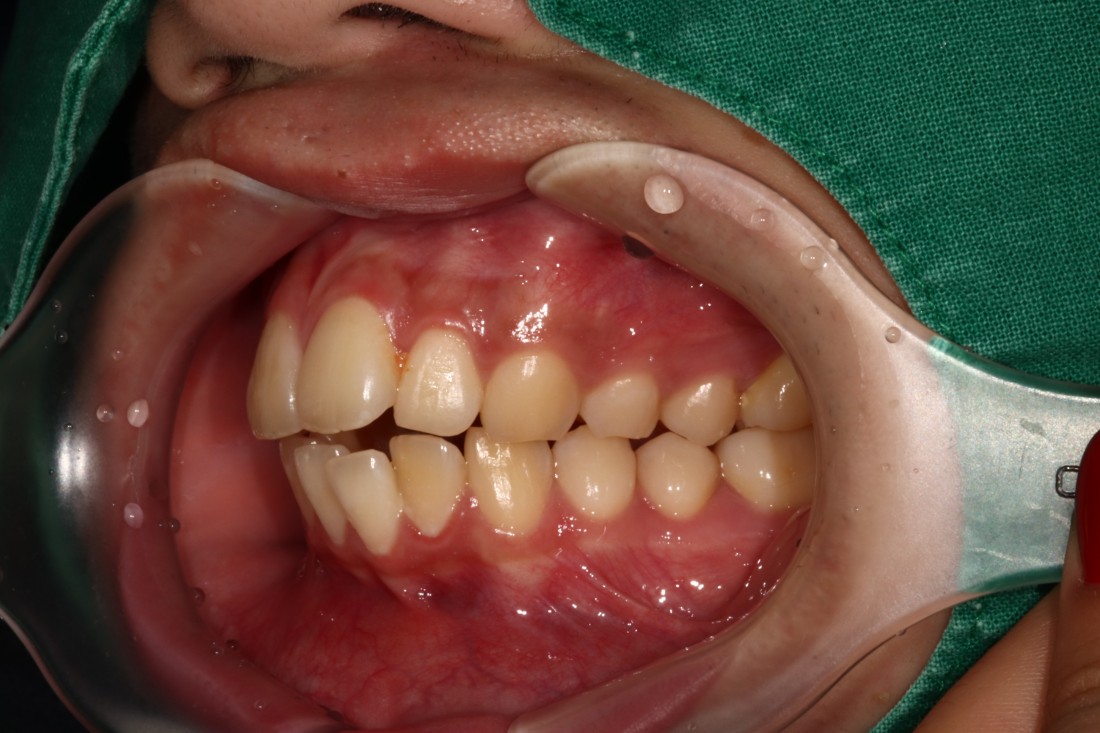

광주 개방교합 교정을 위해

방문해주신 30대 남성 환자분의

교정 전 사진입니다.

어금니를 맞닿게 하여서 입을 다물어도

윗니와 아랫니가 만나지 않는데요.